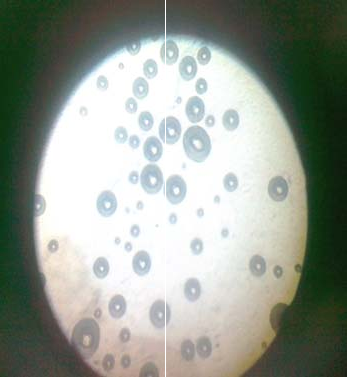

Optical microscopy

The opted formulation (F5) of SEDDS observed under an optical microscope (fig. 1)

The opted formulation (F5) of SEDDS was observed under an optical microscope (Labmed) and it was found that the developed formulation contained the droplets in emulsion (fig. 1).

Fig. 1: Photograph of formulation (F5) of SEDDS of Losartan under an optical microscope